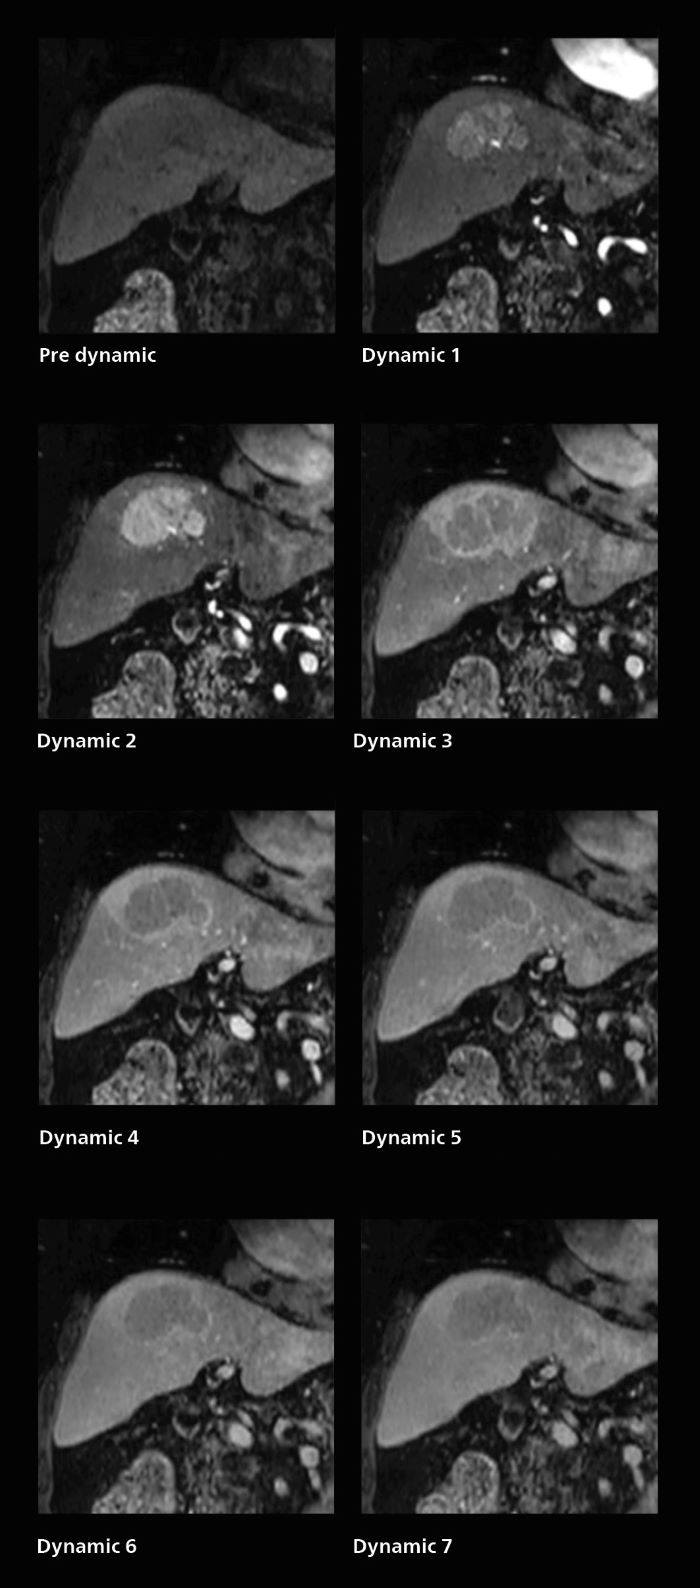

For patients with acute cerebral infarction, who cannot endure long examinations, some clear benefits of SmartSpeed emerge. “We have a fast MR scan protocol that quickly completes the scanning. It allows us to acquire all the images we need in about 3 to 5 minutes,” says Dr. Katahira. “And it is often possible to acquire more images at that level, which is an advantage because the exam is complete even if the patient moves in the middle of the exam.” Also in dynamic MRI of the liver Dr. Katahira sees important improvements. While previously his scan used 9 seconds for a 5 mm slice, SmartSpeed now allows him to achieve a thin slice volume scan (1.6 x 2.1 x 2mm) with double arterial phase using acceleration factor 8. He indicates this is very useful for the radiologist when diagnosing, especially because it can provide a high temporal resolution.

A patient was referred for MR imaging of HCC. A double arterial volume dynamic study was performed. Since it is a volume dynamic study, it can also be evaluated using MPR images. Performed on Elition X.

The hospital’s routine ExamCard for dynamic MRI of the liver uses total scan duration 1:05 min, dynamic scan time 9.2 sec, 1.6 x 1.8 x 2.0 mm, 200 slices, acceleration factor 8.